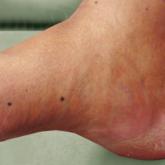

Eruptive Melanocytic Nevi During Azathioprine Therapy for Antisynthetase Syndrome

Eruptive melanocytic nevi (EMN) are rare multiple benign melanocytic nevi that develop within a few months. The phenomenon has been associated...